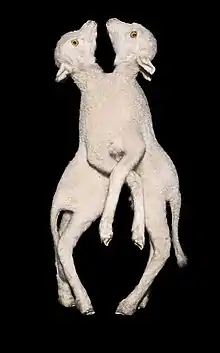

- Tricephalus (conjoined triplets): Extremely rare conjoining of 3 fetuses. Very few confirmed cases, both human and animal, are known.[17]